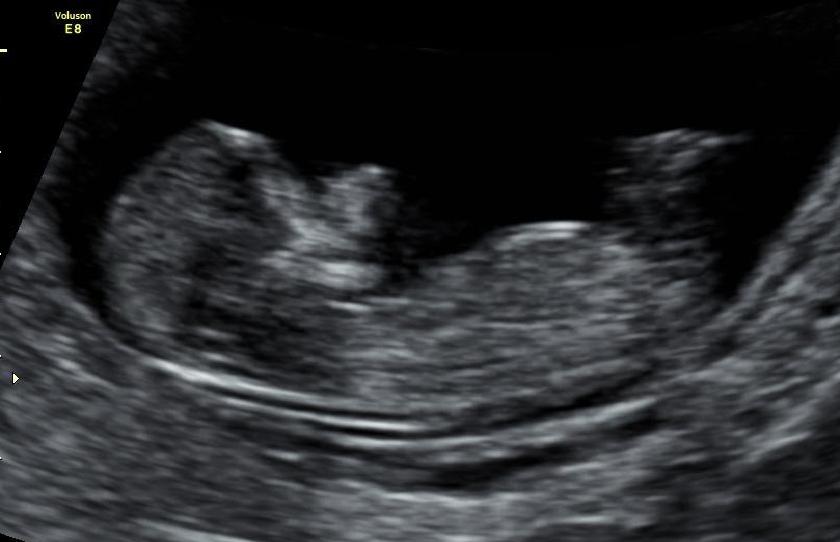

Anyone feel confident to guess my babys 12 week ultrasound please?????Attachment 17236Attachment 17237

It's not a very clear picture, but I will go with girl. I'm not sure if what I can see is a nub or not. If it is, then girl.

Leaning girl. Congrats x

I am thinking girl congrats either way